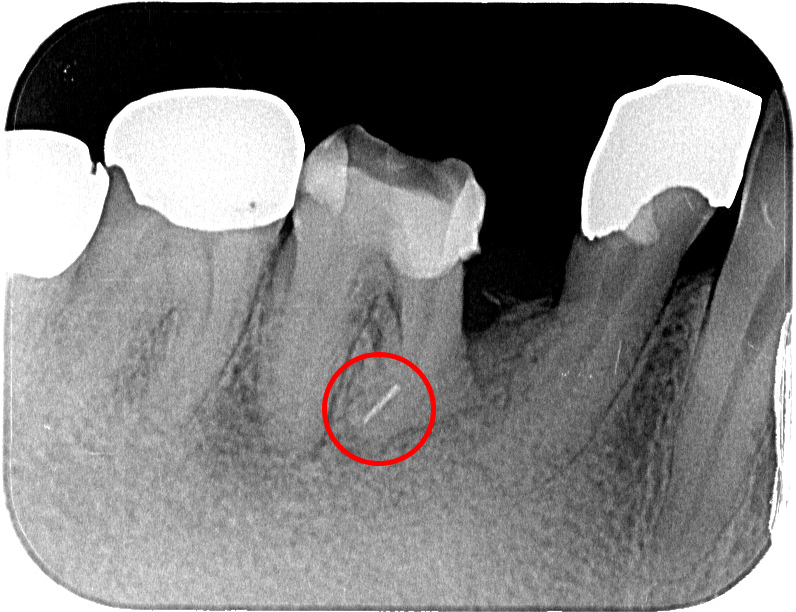

前医で根管治療を行った際、ファイルが破折して歯の中に残ってしまった症例。

超音波で振動を与えて破折ファイルを浮かせることで、安全に除去できる。